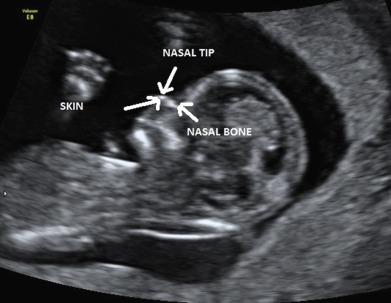

image.png

Down Syndrome in the Womb

Notice the things mentioned